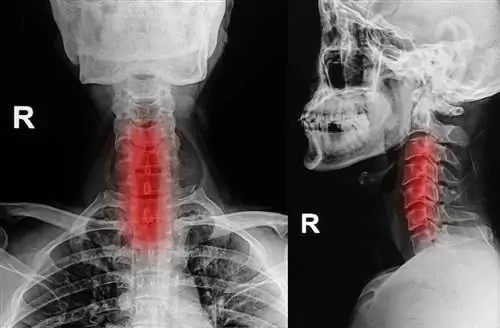

Чтобы выяснить, есть ли у вас шейный кифоз, ваш лечащий врач осмотрит вашу осанку, проверит равновесие и вашу способность свободно двигаться.

Визуализация, такая как рентген или компьютерная томография (КТ), может быть выполнена для подтверждения диагноза.